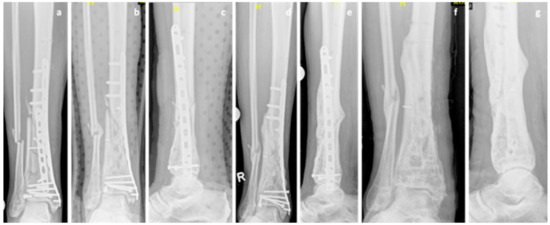

A 77-year-old Caucasian male patient (body mass: 77 kg; height: 178 cm; BMI: 24.3 kg/m2) presented with a grade 2 [15] open fracture of the femur (AO 33 C1) and a closed tibial and fibular fracture (AO 43 A3) following a bicycle accident (collision against a truck). He was treated with an ORIF and plate osteosynthesis of the femur (less invasive stabilization system (LISS) plate, DePuy Synthes, USA) as well as ORIF and plate osteosynthesis of the tibia (distal tibia LCP plate, DePuy Synthes, USA) and fibula (1/3 tubular plate, DePuy Synthes, USA). Eighteen months later an atrophic nonunion was diagnosed and revision surgery of both femur (LISS pate) and tibia (distal tibia LCP plate) was performed. This procedure included decortication, re-osteosynthesis, and application of autologous cancellous bone from the iliac crest. Intraoperative samples showed no sign of infection. The fracture of the femur showed normal healing. Once again, the tibial fracture showed no healing tendency and the diagnosis of an atrophic nonunion (Figure 4a) was made 11 months after the revision surgery operation and 29 months after the initial injury. The patient was referred for further osteological treatment of the tibia. Biomechanical analysis showed a correct anatomical reduction and therefore the decision against further operations was made. Calcium and vitamin D supplementation was initiated and a teriparatide treatment was conducted over a period of 21 months. CTX increased by 83% after the teriparatide therapy. The fracture gap showed gradual callus build-up on the serial x rays (Figure 4b,c). A radiological and clinical union was achieved 4 years after the initial injury (Figure 4d).

Figure 4. Case 4, x-rays showing a nonunion 29 months after the initial injury at the initiation of the teriparatide therapy (a). Serial x-rays after 3 and 15 months of teriparatide treatment showing gradual callus build-up (b,c). Radiological and clinical union was achieved 4 years after the initial injury (d).